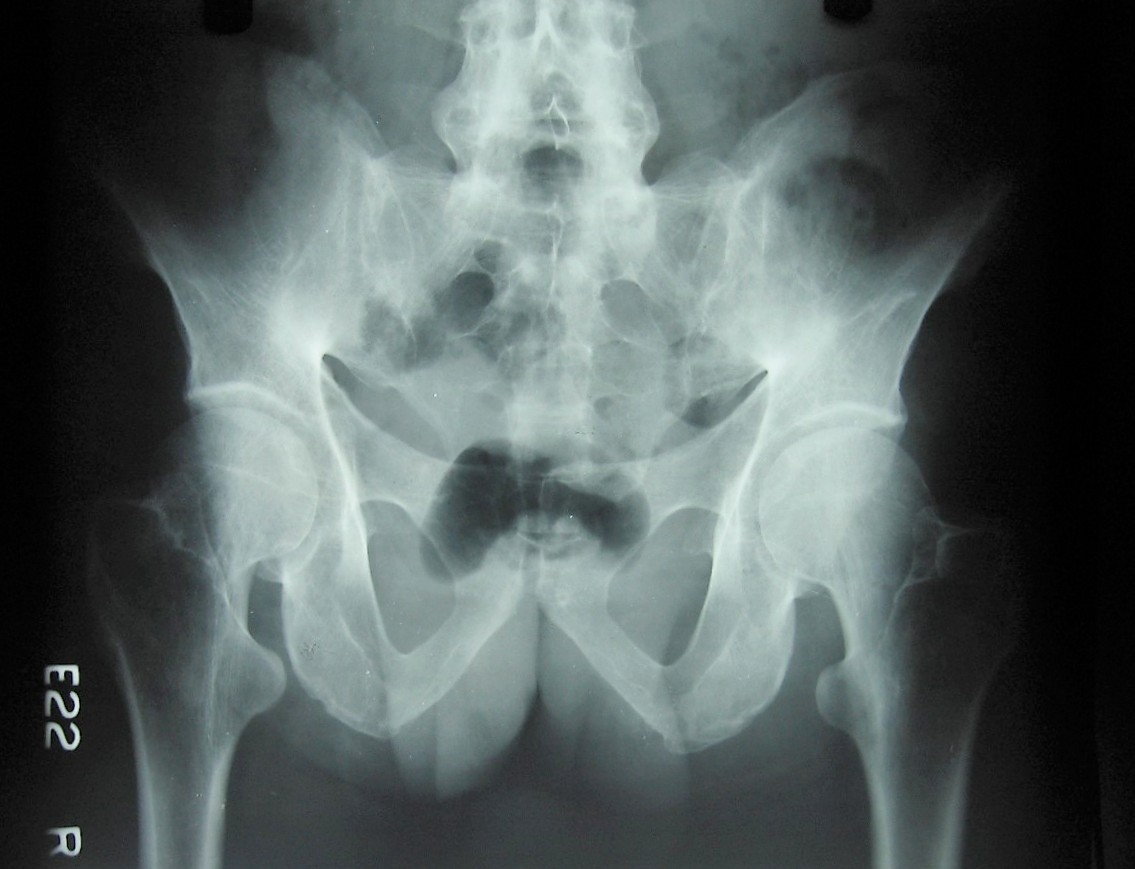

Pelvis A.P view of a 35 year old male